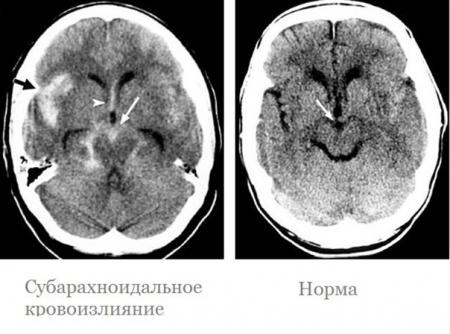

28-летнюю пациентку с кровоизлиянием в мозг спасли коломенские врачи

Молодая женщина поступила в Коломенскую больницу с сильной головной болью и высоким артериальным давлением. В результате проведенной диагностики у пациентки обнаружили кровоизлияние в мозг.